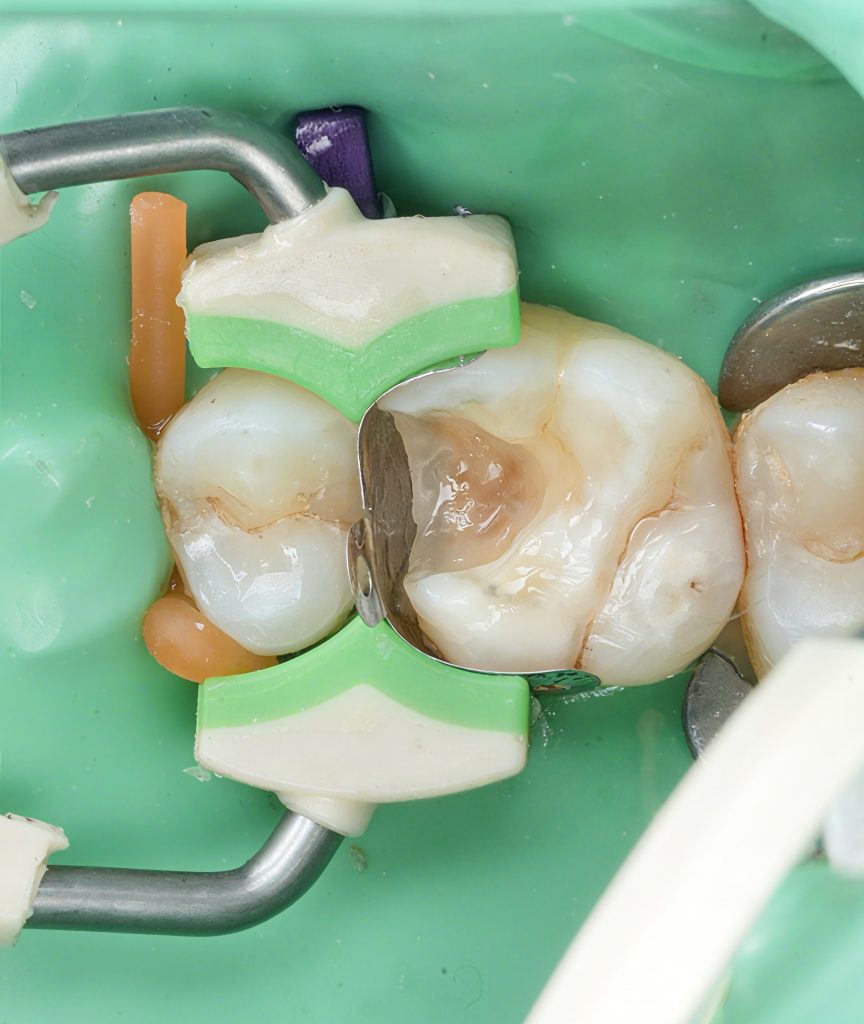

3. Matrix, Wedge & Separation

A tight sectional matrix with a soft wedge gave:

- A clean emergence profile

- Predictable contact strength

- Gingival seal control